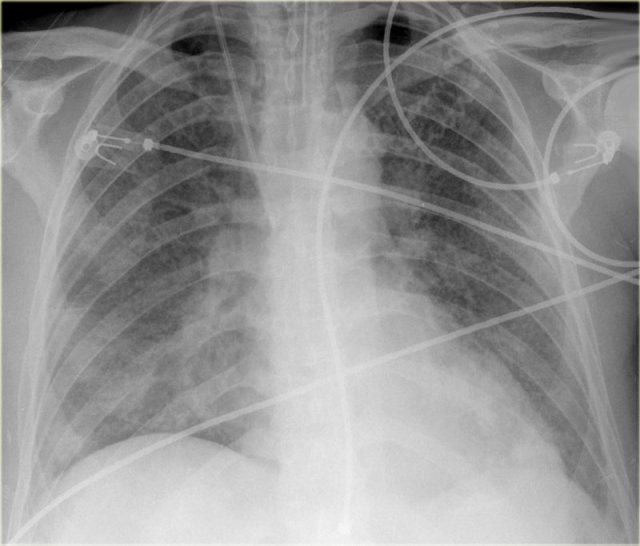

On the left a patient who was admitted with severe dyspnoe due to acute heart failure.

The following signs indicate heart failure: alveolar edema with perihilar consolidations and air bronchograms (yellow arrows); pleural fluid (blue arrow); prominent azygos vein and increased width of the vascular pedicle (red arrow) and an enlarged cardiac silhouette (arrow heads).

After treatment we can still see an enlarged cardiac silhouette, pleural fluid and redistribution of the pulmonary blood flow, but the edema has resolved.